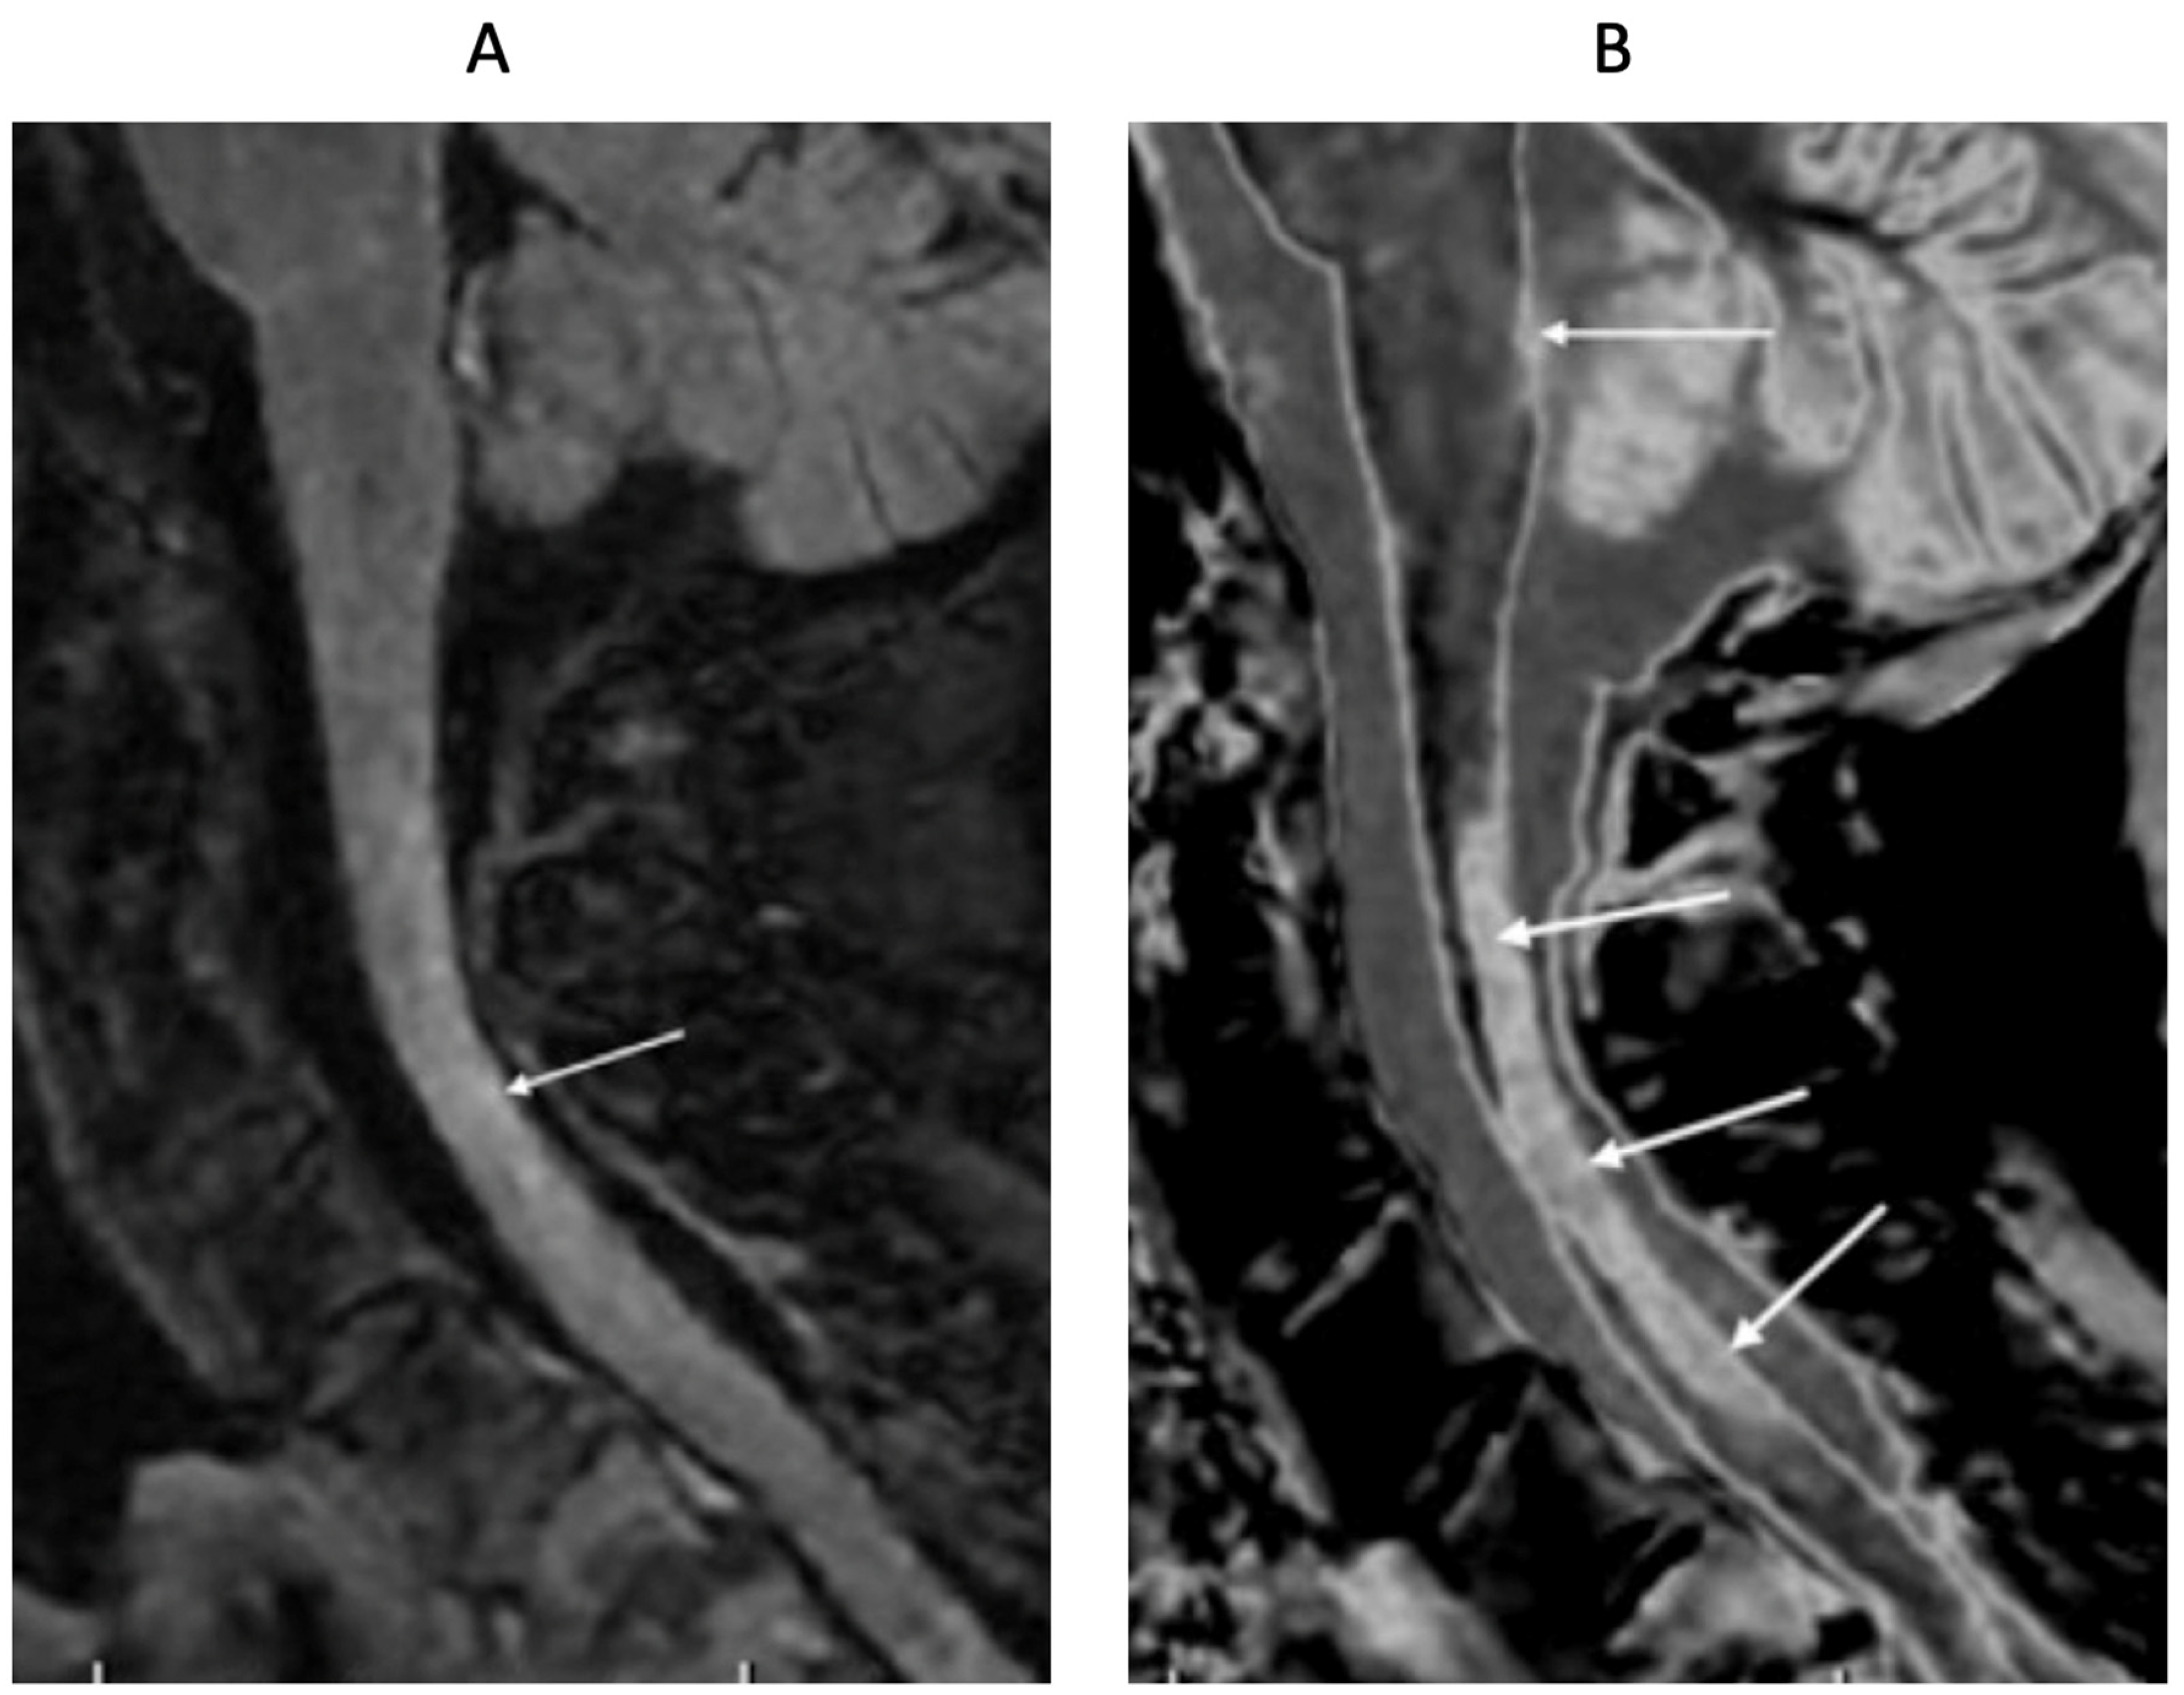

76-year-old female patient in remission with a diagnosis of MS. Sagittal 3D T2-FLAIR (A) and 3D wide mD dSIR (B) images. The T2-FLAIR image shows a poorly defined area of increased signal in the cervical cord (arrow). The dSIR image shows a high contrast lesion with sharply defined ("punched out") boundaries in the cervical cord (lower three arrows). This is much more extensive than in (A). An additional lesion is seen in the medulla on the dSIR image in the region of the area postrema (highest arrow) (B) but not on the T2-FLAIR image (A). The extended lesion in the cervical cord and the lesion in the medulla raise the possibility of neuromyelitis spectrum disorder. Other conventional sequences such as MP-RAGE, T2-wSE or STIR may perform better than T2-FLAIR in the cervical cord.